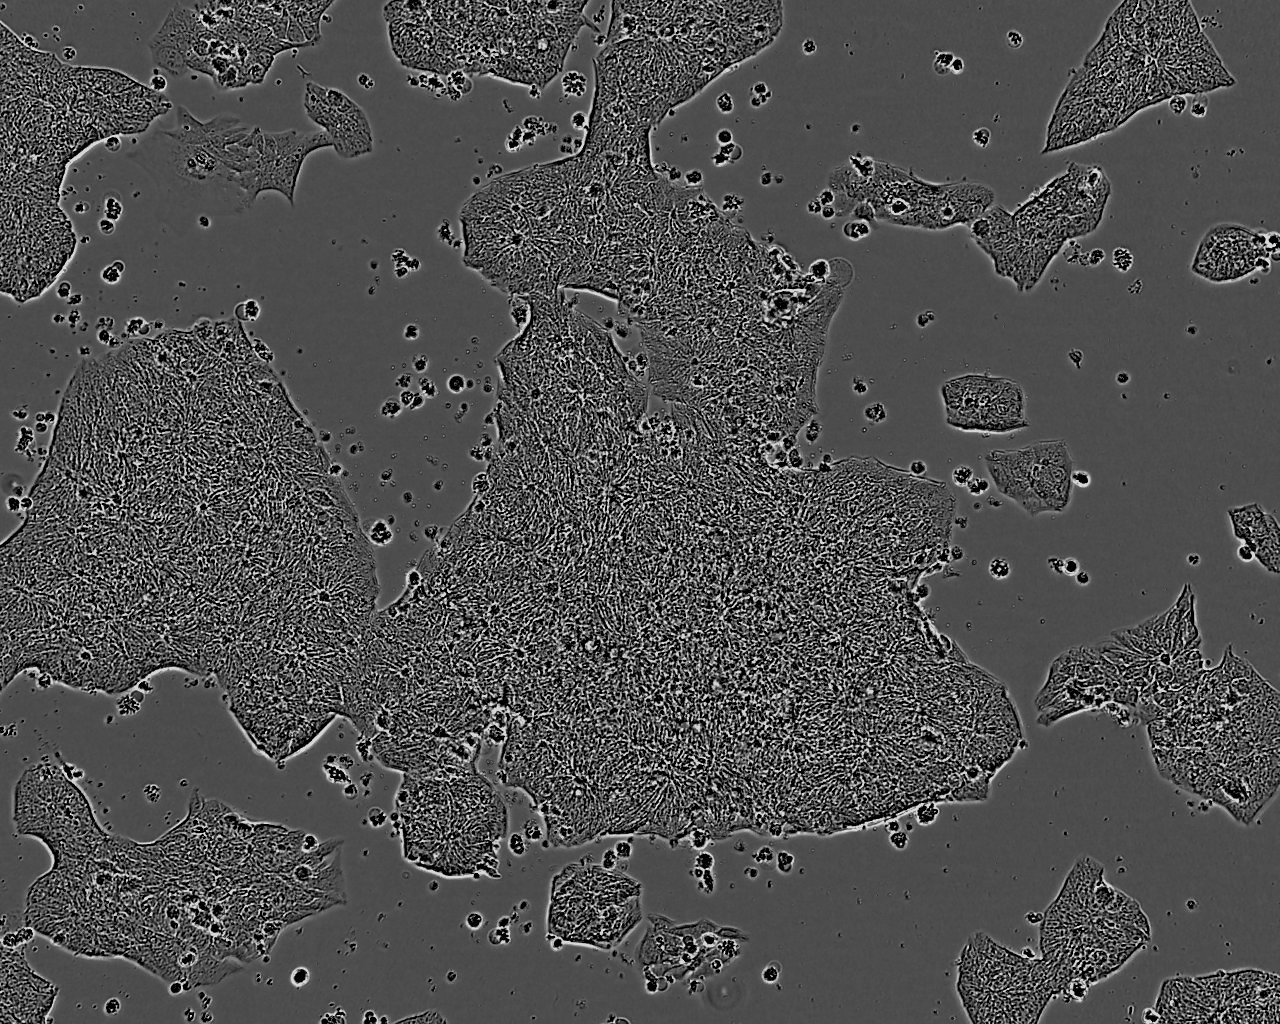

细胞背景资料:DU 145 是从一位有3年淋巴细胞白血病史的前列腺癌患者的脑部转移灶中建立的。该细胞系未检测到激素敏感性,酸性酶阳性,单个的细胞可在软琼脂中形成集落。对此细胞和原始肿瘤的亚显微结构分析可见微绒毛、微丝、细胞桥粒、线粒体、发达的高尔基体和异质溶酶体。该细胞不表达前列腺抗原。

细胞形态:上皮细胞样

细胞生长特性:贴壁